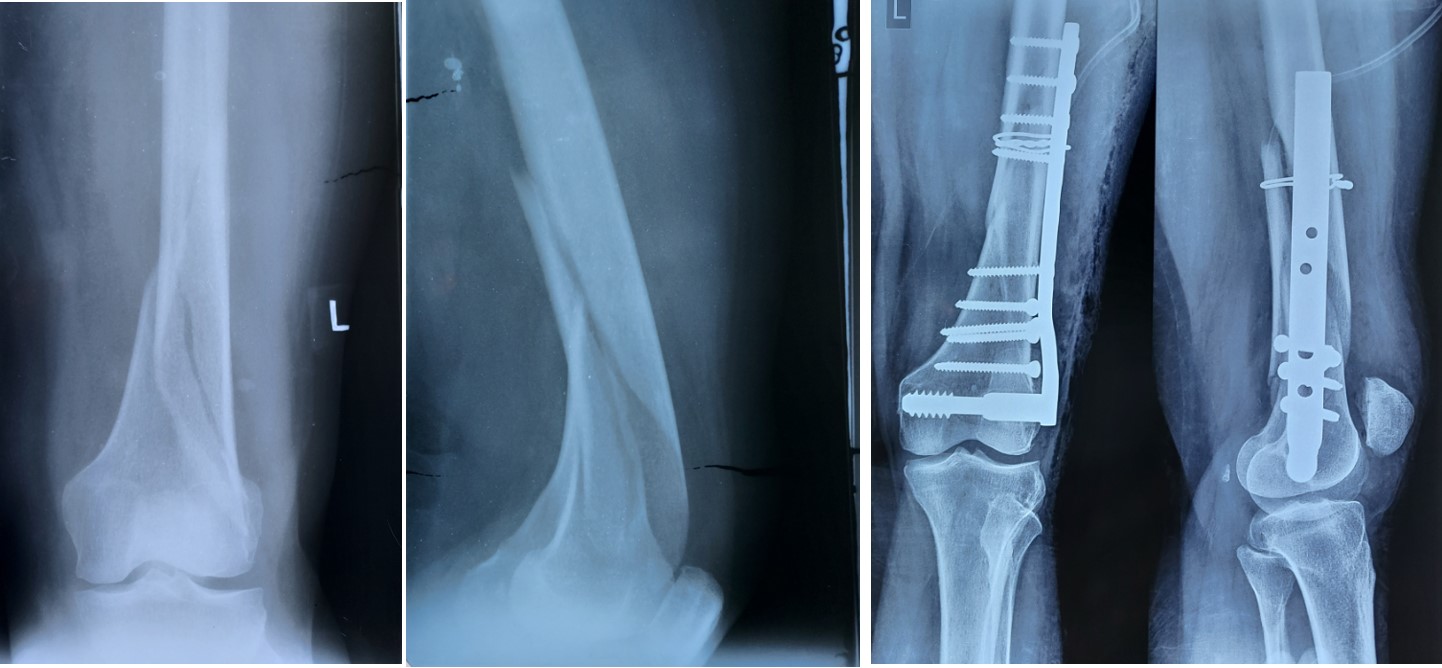

Femer

AVN